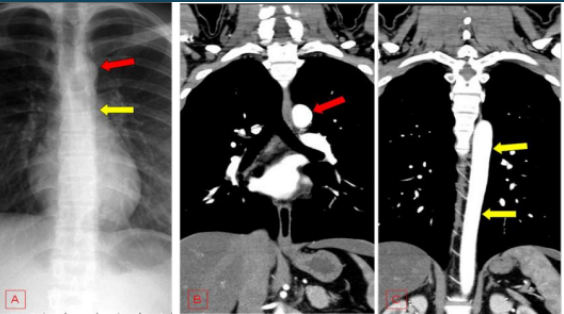

Outras condições: Além dessas, a TC do tórax também é útil para investigar embolia pulmonar, doenças da pleura, aneurismas da aorta, entre outras patologias.

A compreensão da anatomia torácica é fundamental para a interpretação adequada das imagens de TC.

Espaço entre os pulmões contendo coração, grandes vasos, esôfago e traqueia